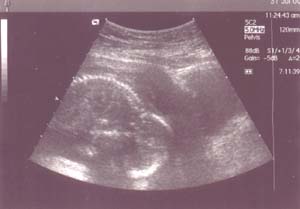

13. týden